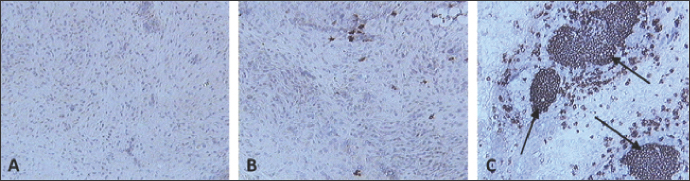

Skin sections were stained using the monoclonal antibody KUL01 (Mast et al., 1998) (Fig. 4). The pattern of macrophage infiltration at the site of vaccination in the skin was similar to that of the virus, as high numbers were detected at 2 dpv and 4 dpv, and these dropped from 6 dpv onwards (Fig. 5).

Fig. 4. Skin sections of birds stained with monoclonal antibody KUL01 against macrophages. Two days post inoculation with (A) PBSa, (B) PHA, and (C) FP9. Positive staining for macrophages appeared brown (100x magnification).

As there are no lymph nodes in chickens, antigen presentation to lymphocytes may occur within the skin tissue (Lu et al., 2023). From Figures 2 and 3 of the present study, the virus was detected in skin tissue after vaccination at a very high concentration at 2 dpv, to a lower degree at 4 dpv and was almost cleared from 6 dpv. The pattern of macrophage infiltration at the site of inoculation in the skin tissue was similar to that of the virus, in that high numbers were observed at 2 dpv and 4 dpv, and these dropped from 6 dpv onwards (Figs. 4 and 5). The concentration of macrophages in the skin at the site of inoculation was higher than that for the birds which were inoculated with PBSa (negative control) and PHA (inflammatory agent), suggesting that the virus might have been taken up by macrophages. In vitro, PHA stimulates T cell proliferation and differentiation while in vivo, the PHA-skin response is an inflammatory reaction, concerning complex interactions of cells—not only lymphocytes but also macrophages and basophils (Restifo et al., 1994).